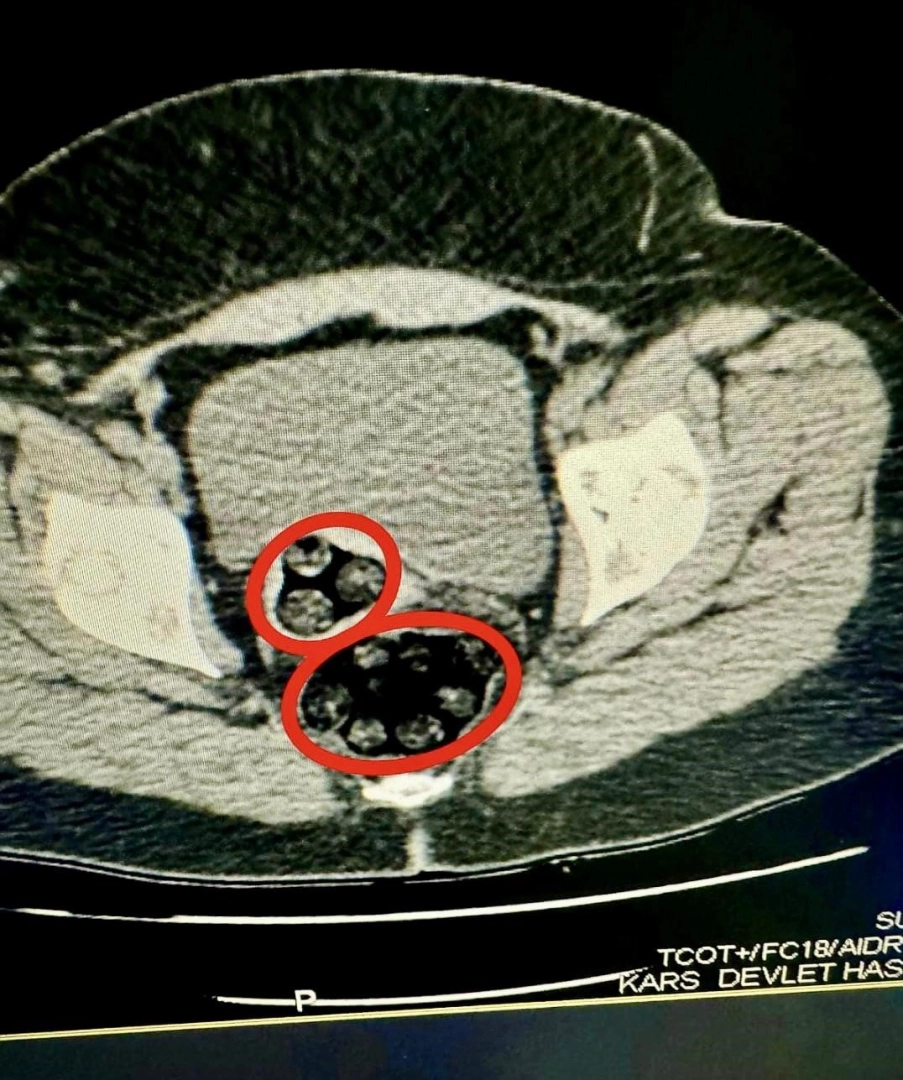

Uyuşturucu kuryesi İranlı kadının makadından 94 parça halinde toplam 550,63 gram uyuşturucu çıktı. Uyuşturucu kuryeliği yapan kadın tutuklandı.Kars il Emniyet Müdürlüğü Narkotik Suçlarla Mücadele Şube Müdürlüğü uluslararası uyuşturucu madde kuryeliği yapan Fahımeh Golmohammadı Yenkejeh’in Kars’a geleceği yönünde bilgi aldı. Bunun üzerine harekete geçen narkotik ekipleri Fahımeh Golmohammadı Yenkejeh’in de içerisinde yolcu olarak bulunduğu ve Iğdır-Trabzon seferini yapan otobüse operasyon düzenledi.94 parça uyuşturucu cerrahi müdahale ile çıkarıldıOtobüste gözaltına Fahımeh Golmohammadı Yenkejeh’in yapılan iç beden muayenesinde makadında cisim olduğu tespit edildi. Fahımeh Golmohammadı Yenkejeh’in makadına saklanmış bir şekilde 94 parça 550,63 gram metamfetamin uyuşturucu maddesi cerrahi müdahaleyle çıkarıldı.Gözaltına alınan Fahımeh Golmohammadı Yenkejeh, İl Emniyet Müdürlüğü’ne getirildi. Burada işlemleri tamamlanan şüpheli, çıkarıldığı mahkemece tutuklanarak cezaevine gönderildi.